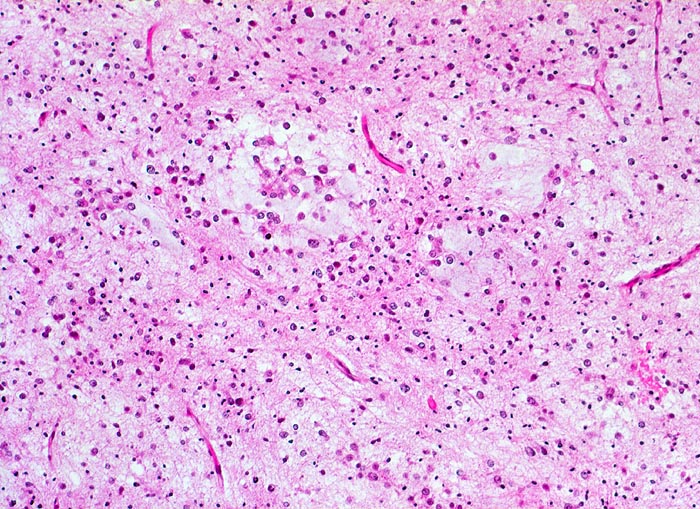

PathoPic – image database / PathoPic ID 5257 - Oligodendrogliom (WHO Grad II)

Oligodendrogliom (WHO Grad II)

Hirn frontal

Das Tumorgewebe enthält zahlreiche kapilläre Gefässe. Das Stroma ist fokal mukoid degeneriert. Der helle Zytoplasmasaum fehlt in diesem Tumorabschnitt.

Kopfschmerzen und epileptische Anfälle seit zwei Jahren.

Histologie

100